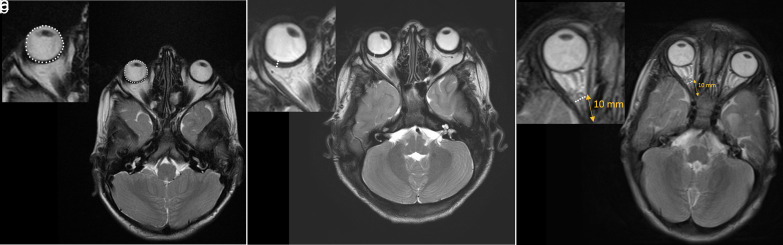

虽然有临床眼科表现的报道,但没有研究记录粘多糖病(MPS) VI型的磁共振成像(MRI)表现。本研究的目的是回顾性确定儿科年龄组粘多糖病(MPS) VI型的眼科影像学表现。方法由两名儿科放射科医生独立评估10例MPS VI型患者和49名健康儿童的脑mri,评估其眼眶体积、眼壁厚度和视神经鞘直径。各组的测量均数采用独立t检验进行比较。通过类内相关系数(ICC)评估评论者之间的一致性和偏倚。结果共59例患儿[女孩32例(54.23%),男孩27例(45.77%);年龄范围4-16岁;平均年龄(10.37±3.73岁)。统计分析显示,MPS VI型患者眼球较小,眼壁较厚(P < 0.001和P < 0.001)。两组视神经鞘直径比较差异无统计学意义(P=.648)。结论与健康儿童相比,MPS VI型患者眼球体积减小,眼壁厚度增加。因此,我们建议眼科影像学结果可能被证明是诊断MPS患者的辅助工具。

PURPOSE lthough clinical ophthalmologic findings have been reported, no study documented magnetic resonance imaging (MRI) findings in mucopolysaccharidosis (MPS) type VI. The aim of this study was to determine the ophthalmologic imaging findings of MPS type VI in the pediatric age group retrospectively. METHODS Brain MRIs of 10 patients with MPS type VI and 49 healthy children were evaluated independently by two pediatric radiologists for the following characteristics: globe volume, ocular wall thickness, and optic nerve sheath diameter for each orbit. The means of the measurement of each group were compared by using an independent t-test. Agreement and bias between reviewers were assessed by intra-class correlation coefficients (ICC). RESULTS A total of 59 children [32 girls (54.23%), 27 boys (45.77%); age range, 4-16 years; mean age, 10.37 ± 3.73 years] were included in the study. Statistical analysis revealed smaller eyeballs and thicker ocular walls of patients with MPS type VI (P < .001 and P < .001, respectively). However, there was no statistically significant difference in terms of optic nerve sheath diameter between the two groups (P=.648). CONCLUSION Patients with MPS type VI displayed reduced globe volumes and increased ocular wall thicknesses compared to the healthy children. Therefore, we recommend that ophthalmologic imaging findings might prove to be an auxiliary tool in the diagnosis of MPS patients.